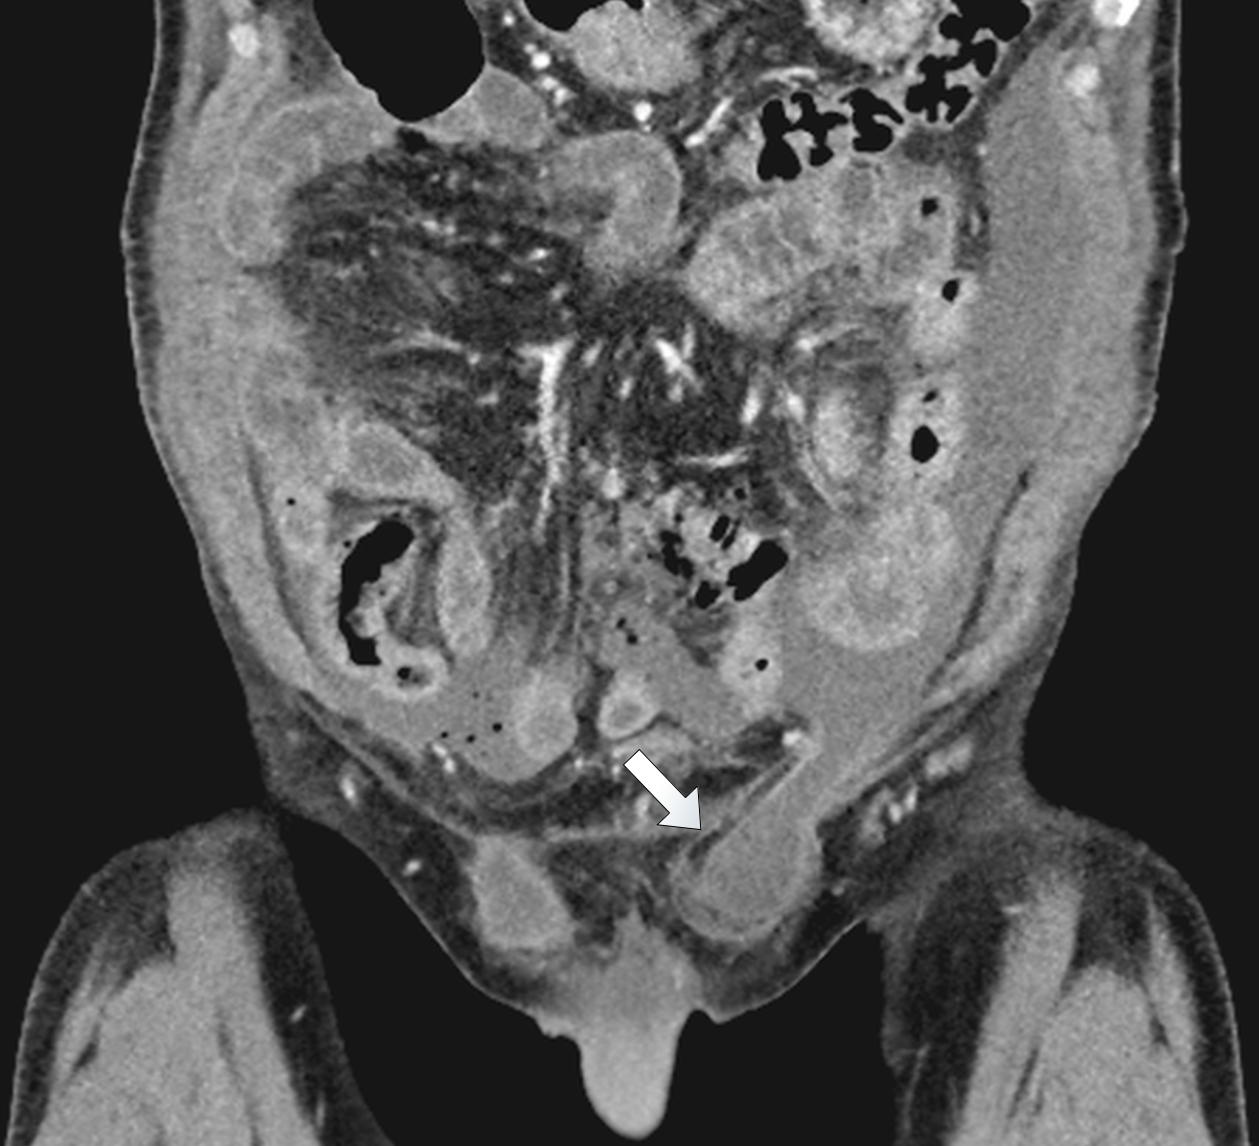

A physically fit 74-year old male with a known history of a left-sided inguinal hernia presented to our emergency department with lower abdominal pain after a fall while playing tennis. After striking the ball the patient fell forward, landed on both his hands and suffered a blunt trauma to his abdomen. He identified a swelling in the left groin and reduced the content back into the abdomen. Due to persisting pain in the lower abdomen he presented to our emergency department. The vital signs were normal and the examination showed tenderness in the lower abdomen without signs of peritonitis. No evidence of incarceration of the inguinal hernia was present. The white blood cell (WBC) count was 13’000 and the c-reactive protein was 17mg/l. The abdominal sonography showed no free fluid or air and the patient was hospitalized for analgesic treatment. Thereby the patient was free of symptoms on the following day. On the second day after the injury the condition of the patient worsened with vomiting and a ballooned abdomen. An erect x-ray of the chest showed free intraabdominal air (Figure 1). The labs showed a WBC count of 6’000, a c-reactive protein of 463mg/l, a creatinine of 136umol/l and normal liver enzymes and lipase. The computed tomography (CT) of the chest and abdomen with intravenous contrast

showed considerable free fluid, free air and a thickened wall of the sigma with multiple diverticula imposing as a pseudotumor without signs of an acute inflammation (Figure 2). This rose the suspicion of a traumatic sigma perforation. The left inguinal canal was fluid-filled with free air present (Figure 3). Because of the absence of an intensive care unit the patient was transported to a tertiary referral hospital for an urgent explorative laparotomy. The inspection showed a feculent 4-quadrant peritonitis with a perforation of the small bowel 50cm proximal to the ileocecal valve. The perforated small bowel was resected as a segment. A side-to-side ileostomy was formed. The sigma was indurated on palpation and suspicious of a colon cancer. In the intraoperative rectoscopy the tumor could not be reached. The inguinal canal was filled with stool and a lavage was performed together with the whole abdomen. A drainage was placed and the abdomen closed temporary with a negative-wound-pressure therapy (NWPT) system. The preoperatively started intravenous antibiotic treatment with imipenem was continued. On the first postoperative day, a rectosigmoidoscopy was unable to pass the stenosis in the sigma. A repeat CT of the abdomen with rectal and intravenous contrast showed wall thickening of the sigma with perifocal lymphadenopathy (Figure 4). In the 2nd look laparotomy 48 hours after the initial operation an anterior resection with complete mesocolic excision and partial mesorectal excision was performed because a malignant disease could not be excluded. A descendorectostomy was performed and the side-to-side ileostomy was reversed into a protective splitstoma. Again, the inguinal hernia was not touched due to the contamination. The NWPT was continued and after two NWPT changes primary fascial closure was achieved eleven days later. The histopathology showed a covered perforation of a sigma diverticulitis with inflamed pseudotumor without signs of malignancy. 22 days after the tennis accident the patient was discharged for rehabilitation. One month later he is in a good health condition and is waiting for the reversal of the stoma and definitive treatment of the inguinal hernia.